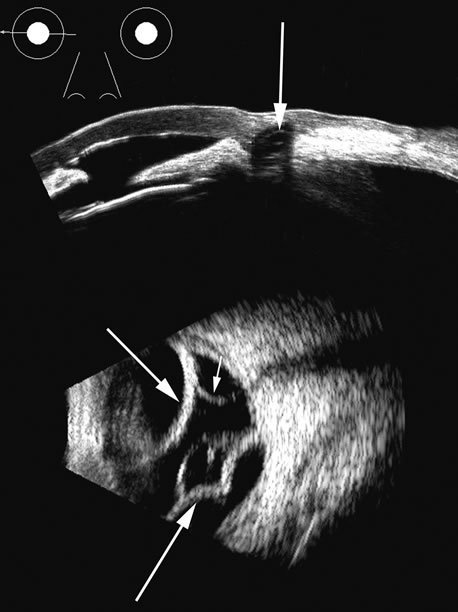

in Medicine. New York, Plenum Press. 1978 14. Coleman DJ, Jack RL: B-scan ultrasonography in diagnosis and management of retinal detachments. Arch Ophthalmol 90:29, 1973 15. Bronson NR, Fisher YL, Pickering NC: Ophthalmic Contact B-Scan Ultrasonography for the Clinician. Westport, CT, International Publication, 1976 16. Downey DB, Nicolle DA, Levin MF, Fenster A: Three-dimensional ultrasound imaging of the eye. Eye 10:75, 1996 17. Coleman DJ, Daly SW, Atencio A, et al: Ultrasonic evaluation of the vitreous and retina. Semin Ophthalmol 13:210, 1998. 18. Wu G, Silverman RH, Coleman DJ, et al: In vivo thickness of human detached retina by ultrasonic signal processing. Graefes Arch Clin Exp Ophthalmol 227:21, 1989 19. Coleman DJ, Rondeau MJ: Diagnostic imaging of ocular and orbital trauma. In Shingleton BJ, Hersh PS, Kenyon KR (eds): Eye Trauma, pp 25–40. St. Louis, Mosby-Year Book, 1991 20. Clemens S, Kroll P, Rochels R: Ultrasonic findings after treatment of retinal detachment by intravitreal

of the posterior segment. Retina 18:251, 1998 42. Atta HR: New applications in ultrasound technology. Br J Ophthalmol 83:1246, 1999 43. Basset O, Gimenez G, Mestas JL, et al: Volume measurement by ultrasonic traverse or sagittal cross-sectional